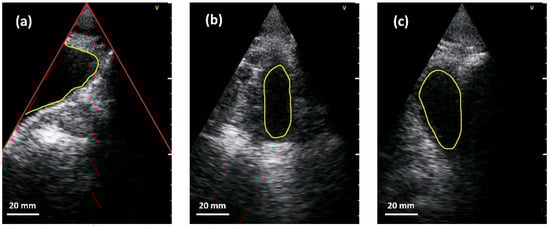

We trained a neural network to segment the bladder into abdominal ultrasound images and encountered two main challenges when implementing the network. On the one hand, the limited space and computational resources available at inference time and on the other hand, the quality of abdominal ultrasound images can be very challenging. Figure 4 shows an example: in the left sub-figure, a (partially filled) bladder appears mainly as a dark region in the image since little sound is reflected by the fluid. In addition, the bladder is only partially imaged and merges seamlessly into the black area outside the ultrasound fan. This situation is usually the case in corpulent patients. As can be seen in the upper part of the segment, weak echoes might occur in cases where the side lobes of the ultrasound beam intersect with the bladder tissue. A very different situation is shown in the middle sub-figure. Here, the (almost empty) bladder is located in the middle of the ultrasound fan. Lastly, the right sub-figure depicts a situation where other anatomical structures, e.g., the pubic bone or the colon, generate a large dark region that might fuse with the bladder. Please note that the appearance of different anatomical parts can be very similar in the images.

Figure 4. Examples of bladder segmentation (yellow). Red lines in the left sub-image indicate the borders of the ultrasound fan above which there is no valid information. (a) Partially visible bladder. (b) Almost empty bladder near the center of the US-fan. (c) Additional dark regions due to pubic bone shadow or colon.